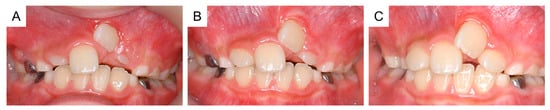

Following surgical exposure, the incisor gradually erupted in the oral cavity (Figure 6). At 9 years and 7 months of age, as confirmed by radiographic examination, no new supernumerary tooth had reoccurred. Intraoral examination revealed mesial inclination of the permanent maxillary left central incisor and a space shortage for the maxillary incisors (Figure 7). The patient is gradually showing an improvement in readiness for dental treatment. Therefore, long-term follow-up will be performed, and orthodontic treatment will be considered according to the wishes of the patient and parents.

Figure 6. Intraoral photographs of the postoperative period. (A) One month after surgical exposure creation (8 years and 10 months of age). (B) Two months after surgical exposure creation (9 years and 0 months). (C) Four months after surgical exposure creation (9 years and 2 months).